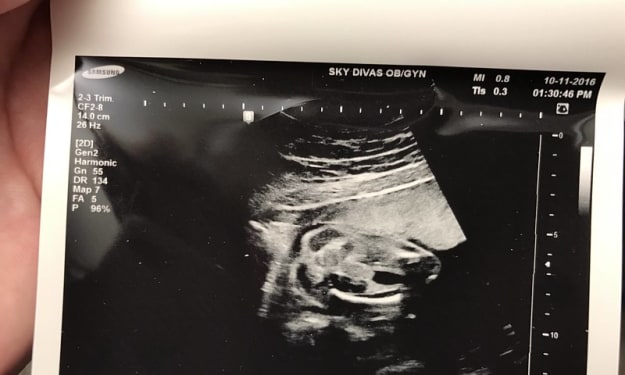

Panorama Results

Results are in and the check-up has been scheduled. In the summer of 2016 it was about 100 degrees in the Denver area. It was hot, I was over-heated. I was taking on a new job and was in the process of moving half way across the country for that promotion. I should have been nicer to myself, but I didn't. I sucked it up and put on my big-girl britches (Wow, where had those maternity pants been all my life? I definitely recommend jumping on that band wagon sooner than later- and for any reason). Although this child was planned, I didn't know I was stacking all of the life-changes on the plate at the same time. Oh hey, Buffet-of-Life, I'll take this and this and this! Yum! Also to my defense, when you have no children you think you can do everything at the same time.

By Hold Still6 years ago in Families